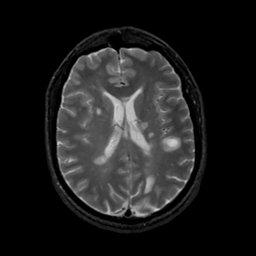

MR Study #16, June 23, 1991 -- Slice #30